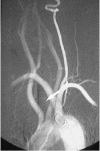

Fig. 2 Arteriogram: The aberrant right subclavian artery arises from the aorta distal to the origin of the left subclavian artery (arrow).